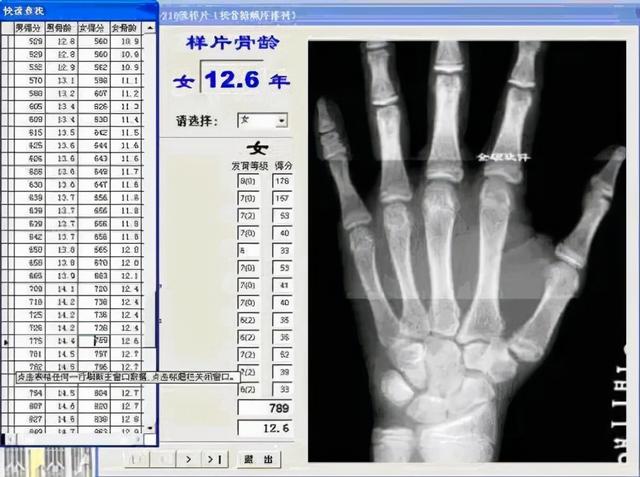

骨龄鉴定。通过个体骨骼的放射影像学特征对青少年的骨骼年龄进行推断。